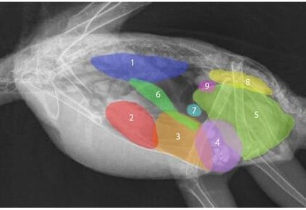

outline this radiograph:

what species

what do we notice about proportions?

what is a disadvantage to this body structure?

in which species do we see this layout?

rabbit

green = heart - rabbit has very small thorax proportional to abdomen, heart is very cranial

any thing can affect lungs and heart from the abdomen, e.g. reproduction as thoracic cavity is so small

hind gut fermenters

What species is this radiograph from and what is important to recognise about it?

it’s large compared to thoracic space, sits vertically against sternum and is very cranial - anatomical location in relation to techniques we may perform

what are the numbers

2= cardiac silhouette

= trachea

where trachea bifurcates to go into different bronchi

caudal vena cava

What species and what are the numbers

1 = diaphragm 2 = cardiac silhouette

= mediastinum which is larger in rabbits